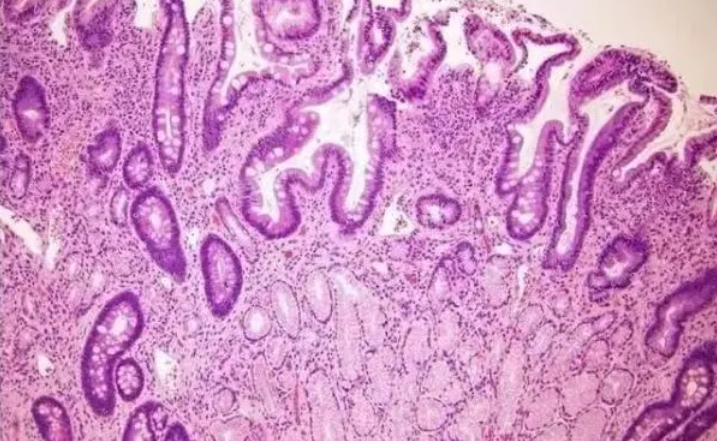

染色的目的是区分组织中各个不同的结构,石蜡切片常用的染色方式为HE染色。在染色前需查看染料的使用时长,使用时间过久的染料着色较浅,会影响染色质量。